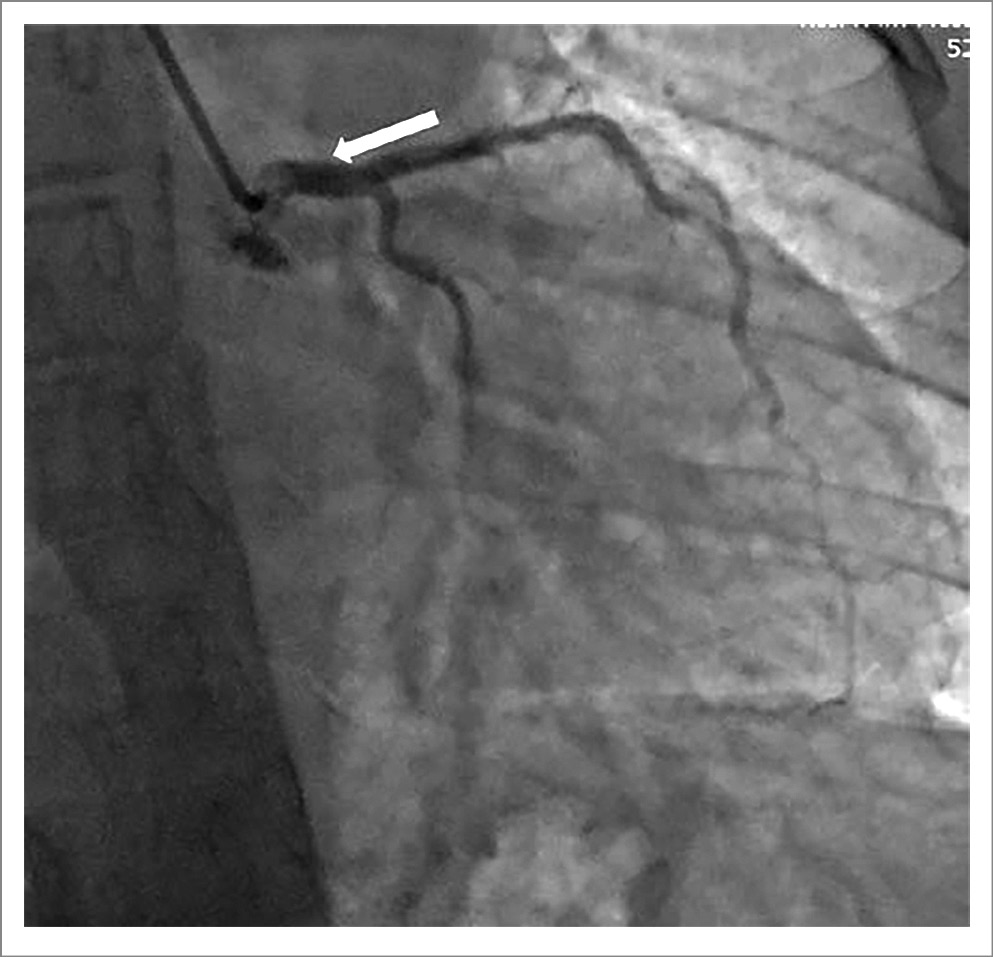

На основании клинических данных и результатов комплексного обследования установлен диагноз: иЛАГ. Стеноз ствола ЛКА за счет компрессии расширенной ЛА. Недостаточность трикуспидального клапана 2-й степени. Хроническая СН2а. ФК3 (Всемирная организация здравоохранения). Учитывая жалобы, высокую степень ЛГ, данные коронарографии, консилиумом принято решение о выполнении эндоваскулярной операции. Поэтому 01.06.2020 выполнена чрескожная транслюминальная коронарная ангиопластика со стентированием ствола ЛКА стентом Калипсо 4,0×11 мм (рис. 2).

Рис. 2. Коронарография. Стентированный сегмент ствола ЛКА указан белой стрелкой.